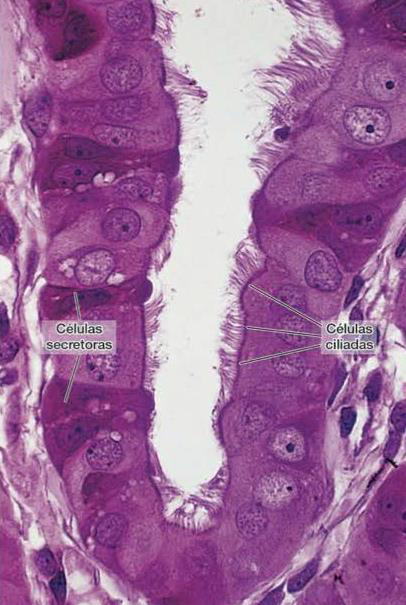

É um tubo enovelado chamado ducto epididímário, dividido em: cabeça, corpo e cauda. A cabeça e corpo é responsável por fazer a maturação espermática. A cauda armazena os espermatózoides até acontecer a ejaculção para a liberação desses espermatozoides.

O epitélio do ducto epididimário é do tipo pseudo-estratificado com a presença de estereocílios (estrutura com a finalidade de auxuliar a movimentação dos espermatozoides).

Epididímo. Coloração H&E Fonte: https://histologia.icb.ufg.br/masc.html#_ |